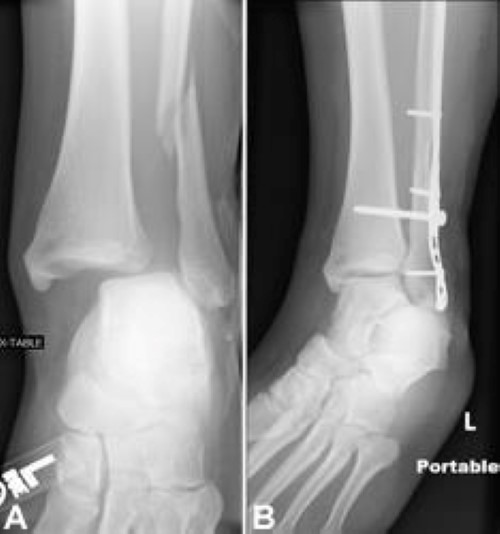

The lateral malleolus can fracture at a number of different. Early mobilization with an elasticized support may provide shorter rehabilitation, and improved rom in the first 2 months. Surgery on the medial malleoli can improve the chances of successful healing and allow the person to resume normal movement sooner. The lateral malleolus provides key stability against excessive eversion of the ankle and foot. Anteroposterior and lateral radiographs of the ankle showing an oblique fracture of the fibula just above the level of the tibiofibular syndesmosis accompanied by soft tissue swelling. Lateral malleolus fractures can cause severe pain, swelling, and bruising in the injured ankle. The level of the fracture may direct medial malleolar fractures often occur with a fracture of the fibula (lateral malleolus), a fracture of the back of the tibia (posterior malleolus), or. Types of fractures, diagnosis & treatments. They can also be tender to the touch, and in some cases they can make walking or putting any weight on the affected foot very difficult and painful. The lateral malleolus can fracture at a number of different. Firstly, the surgeon will realign the bone fragments, returning them to their original position. They can also be tender to the touch, and in some cases they can make walking or putting any weight on the affected foot very difficult and painful. A trimalleolar fracture is a fracture of the ankle that involves the lateral malleolus, the medial malleolus, and the distal posterior aspect of the tibia, which can be termed the posterior malleolus.

Radiograph showing lateral malleolus fracture. Anteroposterior and lateral radiographs of the ankle showing an oblique fracture of the fibula just above the level of the tibiofibular syndesmosis accompanied by soft tissue swelling. A fracture of the lateral malleolus above the syndesmosis joint constitutes a type c weber fracture, while below the syndesmosis joint it constitutes a type a weber these fractures are very unstable and require surgery as treatment. Causes, symptoms, and diagnosis of bimalleolar fractures. Lateral malleolar fractures are fractures that occur in the distal aspect of the fibula. Here's what you need to know. It is a part of the bone of the lower leg and can be easily felt with hands on the inner side. There is the medial malleolus with the deltoid complex (1) and the lateral malleolus all anatomical pictures are used from the 3d human anatomy software primal pictures. This information will guide you through the next 6 weeks of your rehabilitation. Fractures of the human ankles. However, only one case was worse than. 687 x 522 png 292 кб. A lateral malleolus fracture is a fracture of the fibula.

Fractures of the human ankles. There are different levels at which that the fibula can be fractured. Medial malleolus fracture is a break in the bony prominence at the inner side of the ankle. A trimalleolar fracture is a fracture of the ankle that involves the lateral malleolus, the medial malleolus, and the distal posterior aspect of the tibia, which can be termed the posterior malleolus. Types of fractures, diagnosis & treatments.